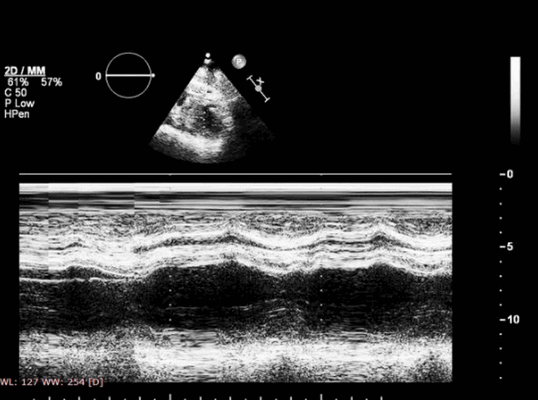

Указанные изменения можно обнаружить с помощью двумерной эхокардиографии, но M-режим также чрезвычайно хорош, поскольку его высокая частота дискретизации делает его очень чувствительным к движению стенок и аномалиям утолщения. Важно, чтобы курсор располагался под углом 90° к стенке. Есть ограниченные области миокарда ЛЖ, которые можно исследовать в М-режиме - наиболее полезно задняя стенка и МЖП. Изменения обратимы, если ишемия кратковременная, например в покое, прием антиангинальных препаратов, проведенная вовремя чрескожная транслюминальная коронарная ангиопластика, тромболизис или аортокоронарное шунтирование (АКШ). Если кровоснабжение миокарда прервано более чем на 1 час, происходят необратимые изменения, включающие инфаркт миокарда и рубцевание.

Рисунок 2. Выраженная эксцентричная гипертрофия левого желудочка с толщиной межжелудочковой перегородки 2,8 см у больного с гипертрофической кардиомиопатией.